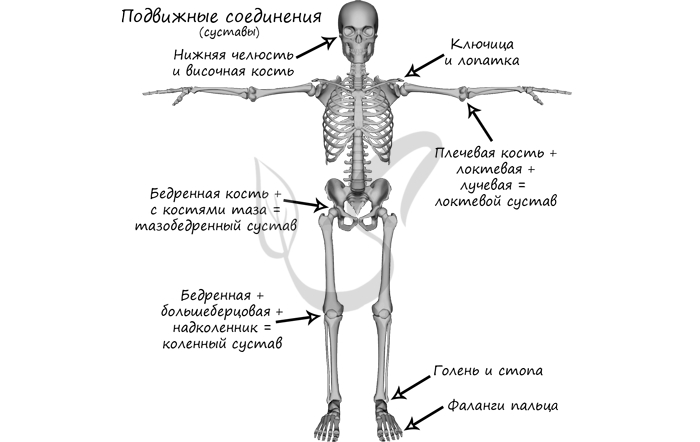

Соединения костей

Кости могут быть соединены друг с другом неподвижно: кости таза (подвздошная, лобковая, седалищная), кости черепа (кроме нижней челюсти), позвонки крестцового отдела, копчик.

Подвижно в скелете человека соединены: нижняя челюсть + височная кость, ключица + лопатка (сустав малоподвижен), бедренная кость + тазовая кость (тазобедренный сустав), плечевая кость + локтевая + лучевая (локтевой сустав), бедренная + большеберцовая + надколенник (коленный сустав), голень и стопа (голеностопный сустав = большеберцовая + малоберцовая + таранная кости), фаланги пальцев.